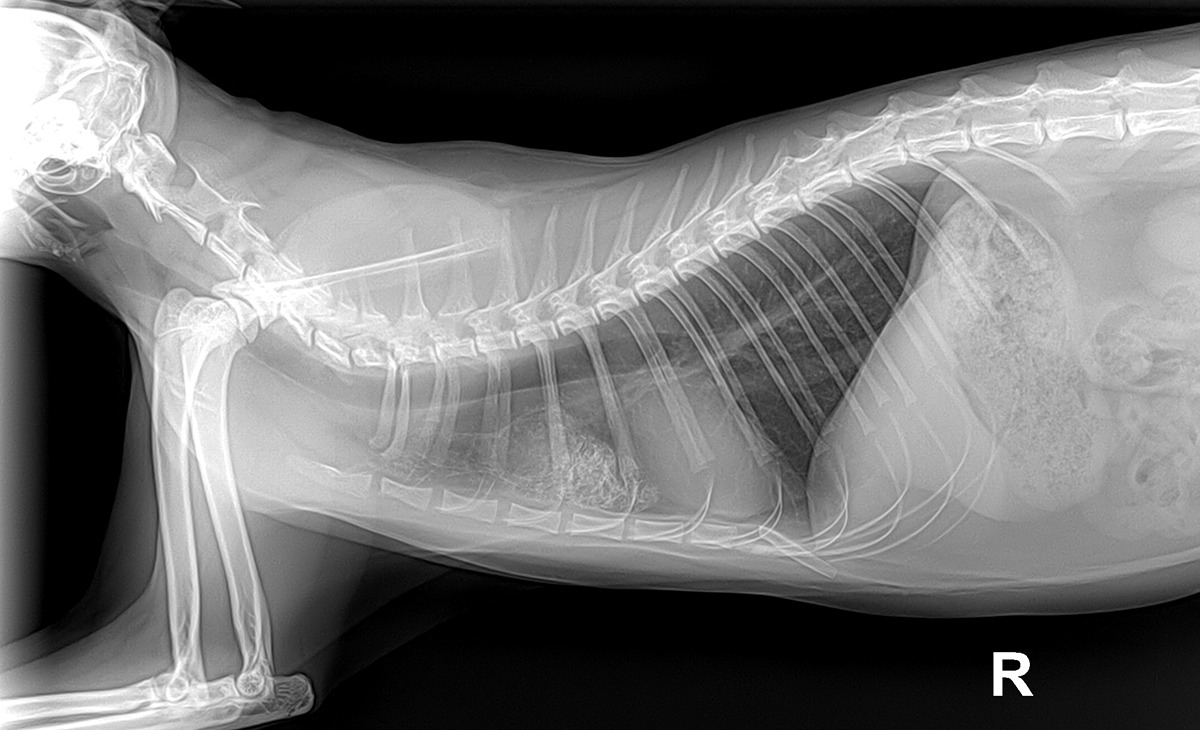

제이0.jpg 항암치료 4주차의 엑스레이